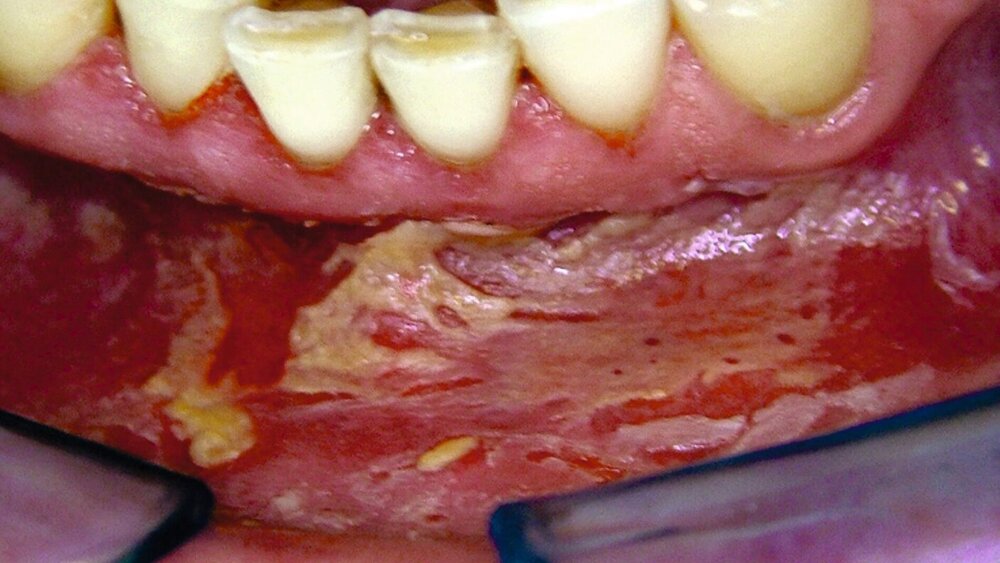

In der PRISCUS-Liste wird explizit auf die gastrointestinalen Nebenwirkungen der NSAR wie Ulzerationen und Blutungen hingewiesen. Diese Ulzerationen können bei unsachgemäßer Anwendung auch im oralen Bereich auftreten (Abbildung).